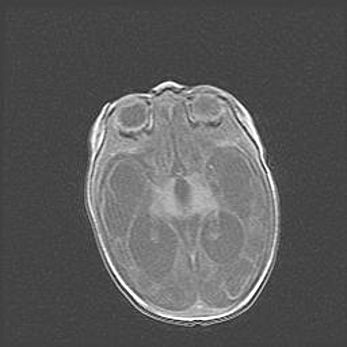

Множественные кисты обоих полушарий головного мозга, наибольшая из них в правой затылочной области. Ассиметричная атрофическая гидроцефалия.

Возраст: 7 месяцев

Вес: 5660 г

Пол: мужской

Окружность головы: 41,5 см

Срок гестации: 28-29 недель

Кисты головного мозга развиваются в результате многоочаговых некрозов вещества мозга и возникают вследствие перенесенной перинатальной инфекции, менингитов, энцефалитов, асфиксии, родовой травмы, расстройств мозгового кровообращения различного генеза. Образованию кист в веществе головного мозга плодов и новорожденных способствуют такие факторы, как высокое содержание в нем воды, недостаточная (или отсутствие) миелинизация и слабая астроглиальная реакция на повреждение.

Кисты могут сочетаться с гидроцефалией и другими поражениями головного мозга.